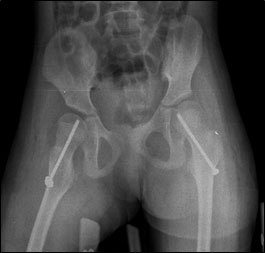

Developmental dysplasia of the spastic hip (DDSH, Portinaro et al 2007) is the most frequent malformation in Cerebral Palsy.

It is a dislocation which is not present at birth, but that develops progressively over the years and it is due to a number of factors such as spasticity, retraction of muscles, inappropriate muscle control, lack of load and unhealthy posture of patients affected by this condition.

These factors can trigger a process whereby the femur progressively moves away from its socket until complete dislocation, which occurs when the femoral head is completely out of the acetabulum and the two articular surfaces are no longer in contact with each other.